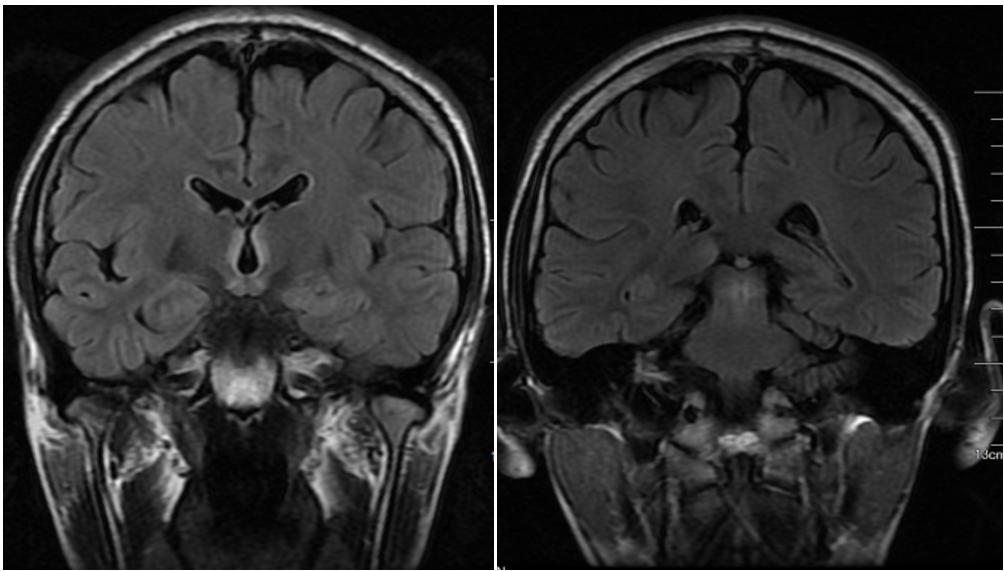

男,54歲,白血病病史。臨床表現(xiàn)為意識障礙、共濟失調。Flair示高信號位于雙側舌下神經(jīng)核(A)、前庭神經(jīng)內側核(B)、面神經(jīng)核(長箭頭)和展神經(jīng)核(短箭頭)(C)、中腦頂蓋和導水管周圍灰質(D)、乳頭體(E)、下丘腦和第三腦室周(F)。